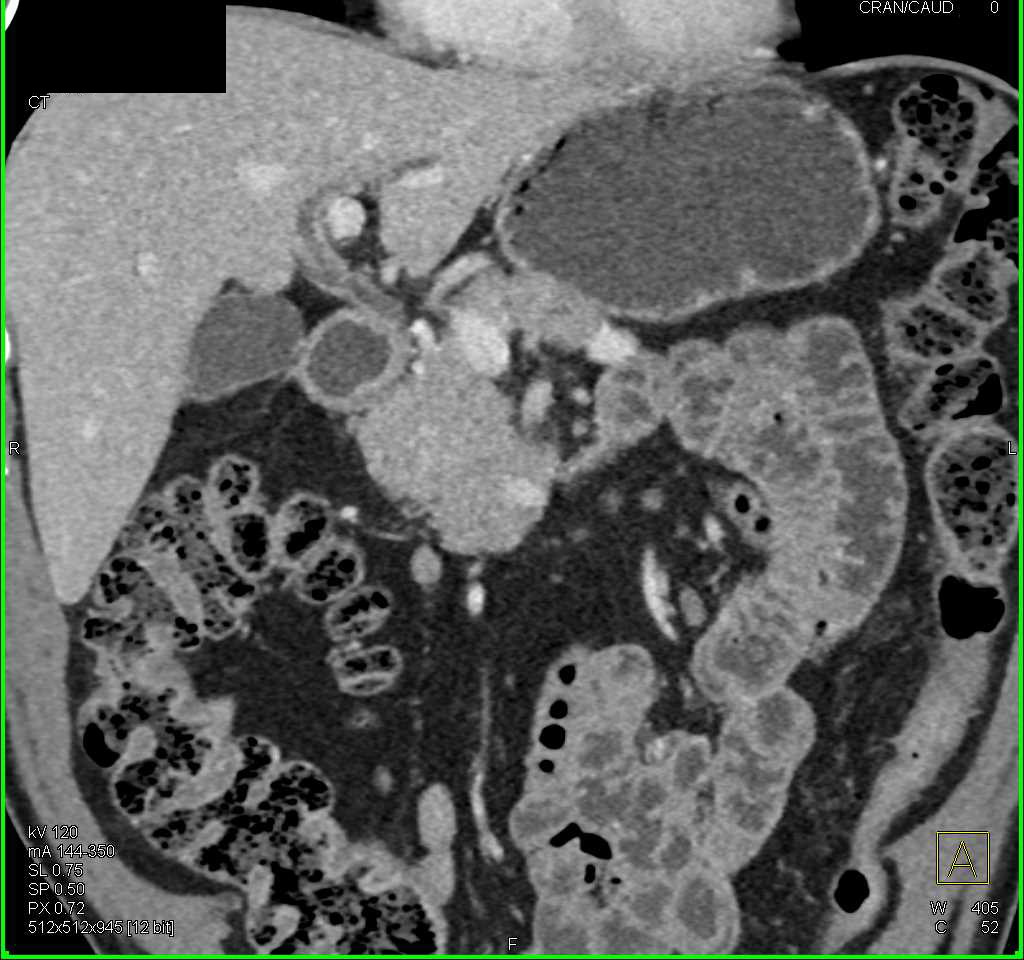

Hepatic Artery Bleed s/p Whipple Procedure